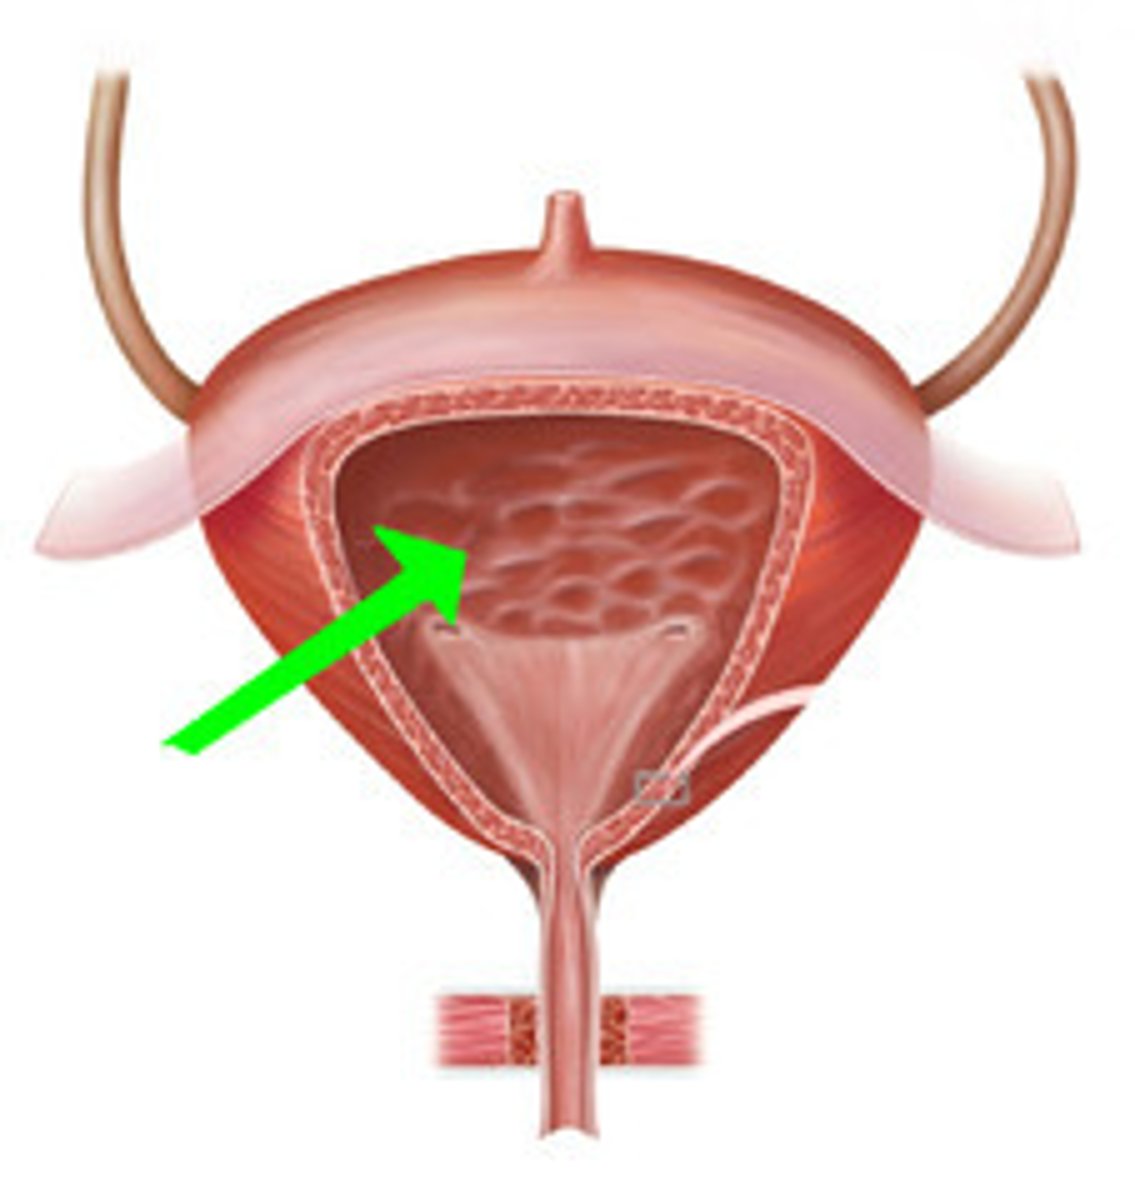

urinary bladder

urinary bladder

detrusor muscle

layer

internal urethral sphincter

bladder neck

external urethral sphincter

ureteric orifice

trigone of bladder

rugae

Urethra